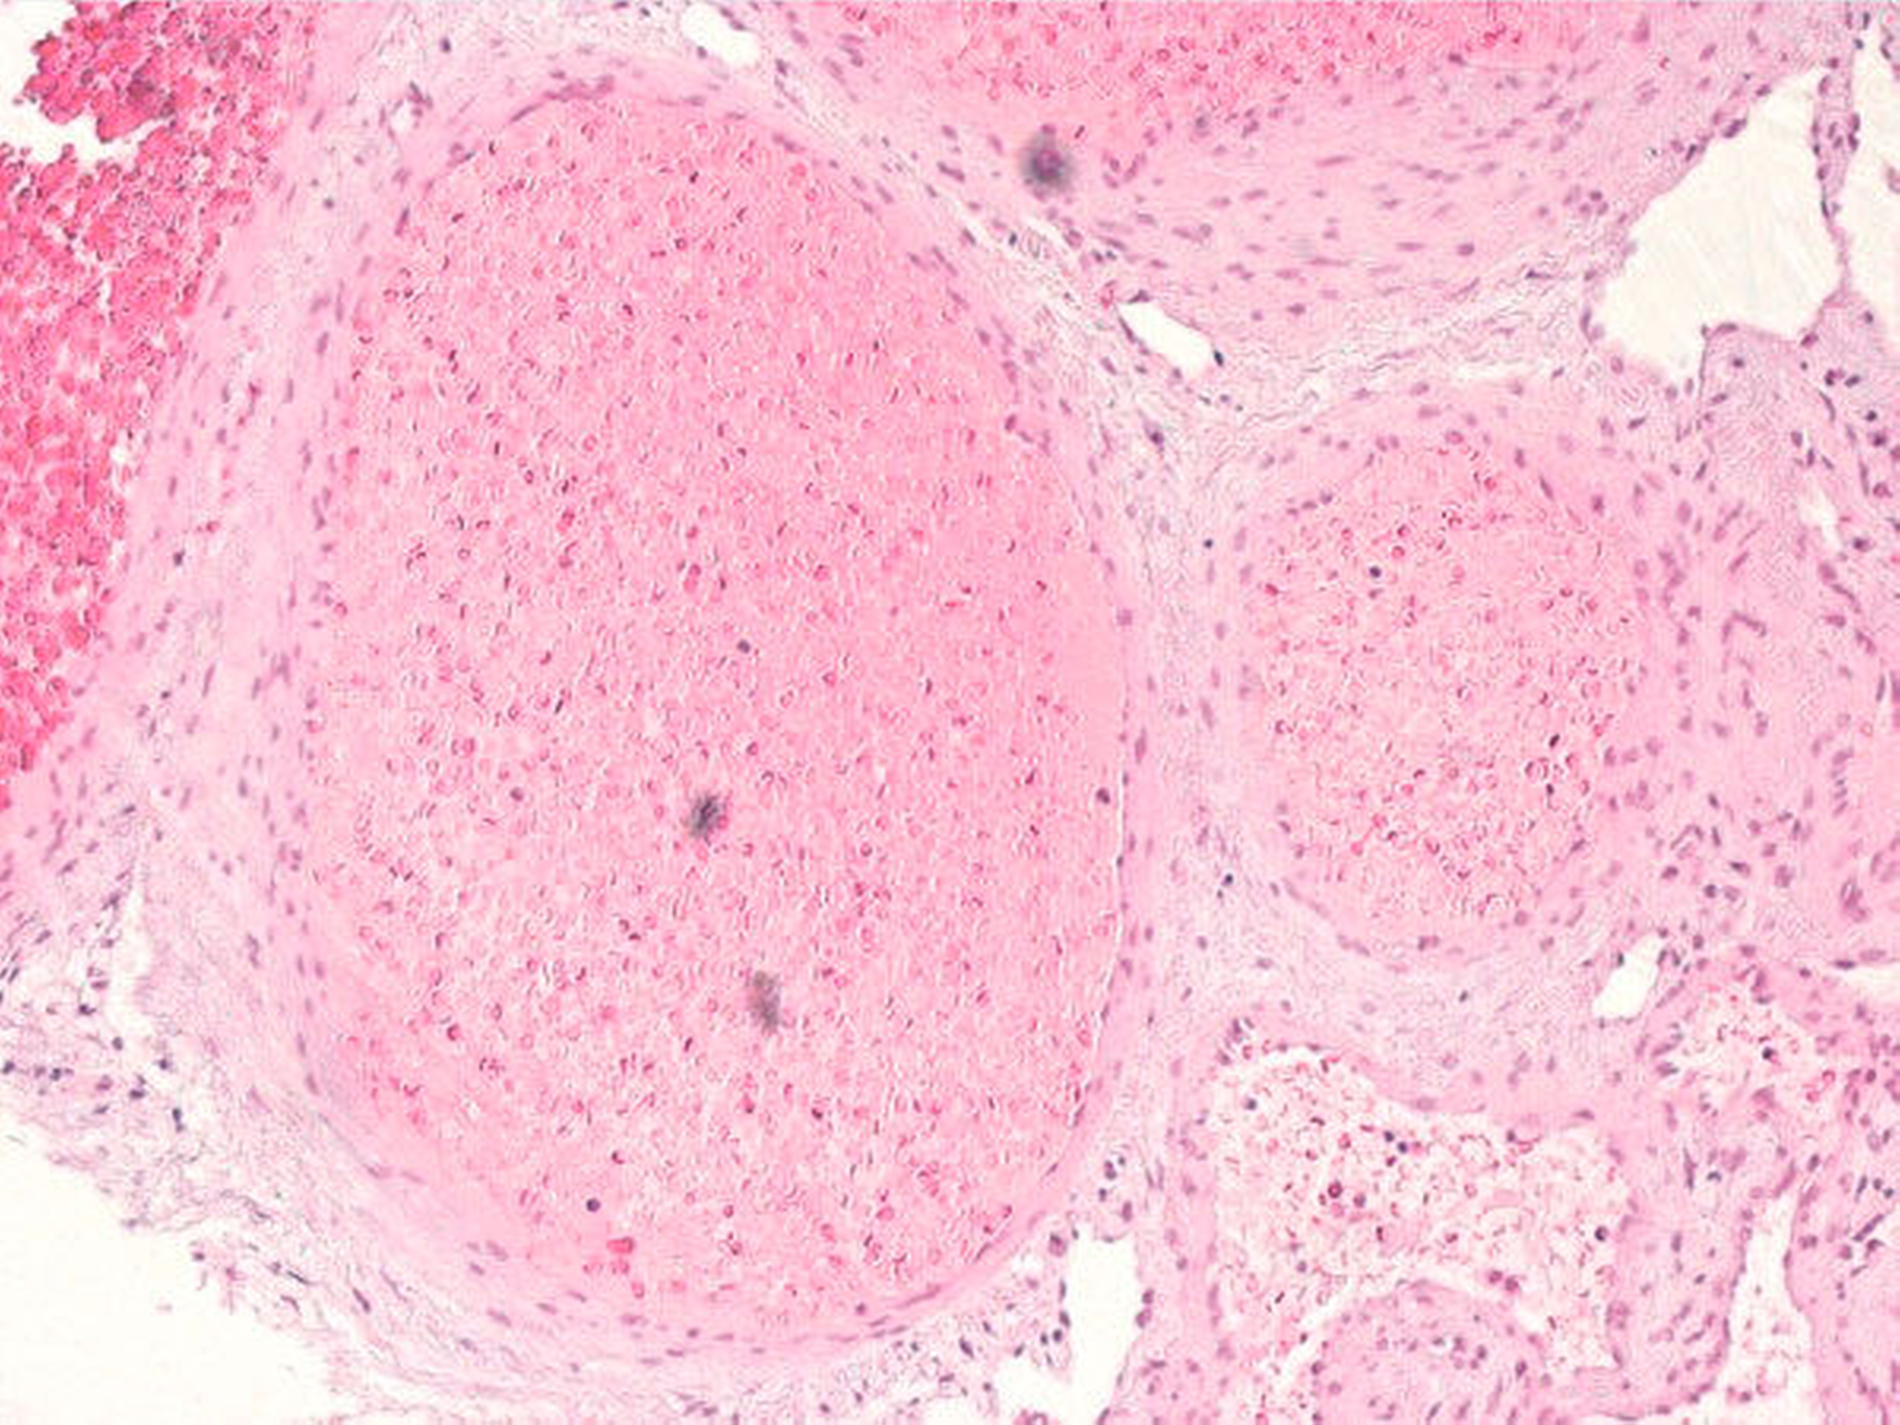

Die histopathologische Aufbereitung des Präparats (Abbildung 7) erbrachte den Nachweis eines kavernösen Hämangioms ohne den Anhalt auf Gewebetransformation (Abbildung 8). Der postoperative Verlauf gestaltete sich bis auf eine kurzfristig bestehende Wunddehiszenz mit sekundärer Granulation unauffällig. Sensibilitätsdefizite bestanden zu keiner Zeit.

Histologisch wird das Hämangiom in eine kapilläre, eine kavernöse und eine gemischte Variante eingeteilt, wobei die meisten Tumore vom kavernösen Typ sind. Diese zeichnen sich vor allem durch mitotische Aktivität, große vaskuläre Strukturen und eine lang andauernde klinische Anamnese aus. Endothelzellen proliferieren und bilden ein plexiformes vaskuläres Muster. Die dünnwandigen kavernösen Räume sind von einer einzelnen Schicht aus Endothelzellen umgeben, die zwischen den ossären Trabekeln verteilt sind.